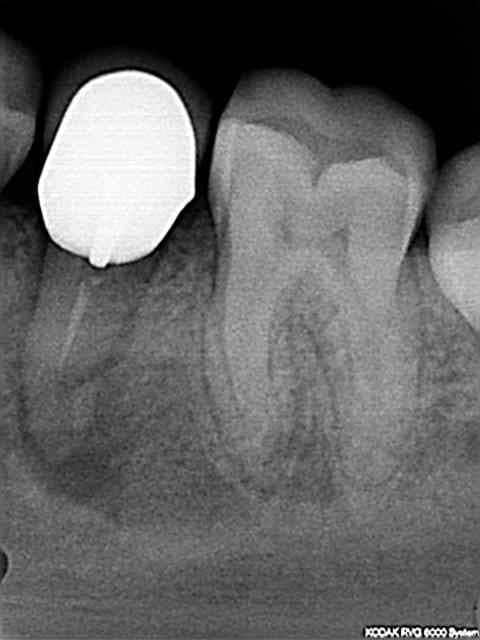

Voici un cas réalisé ce matin.

Reprise sur une 35 couronnée en Mai dernier dans un centre de soins.....

Commentaires des radios envoyées dans le message précédent : En 15 minutes, instrument 25 pour désobturer, préparer et prendre la longueur de travail. Instrument Niti 25 Endo Express pour la conicité.

Instrument 30, puis 35 et enfin le dernier instrument conicité 8%.

Obturation thermomécanique à 35/100 avec le ciment EZ-Fill (epoxy) remarquez les canaux latéraux et la densité de l'obturation.